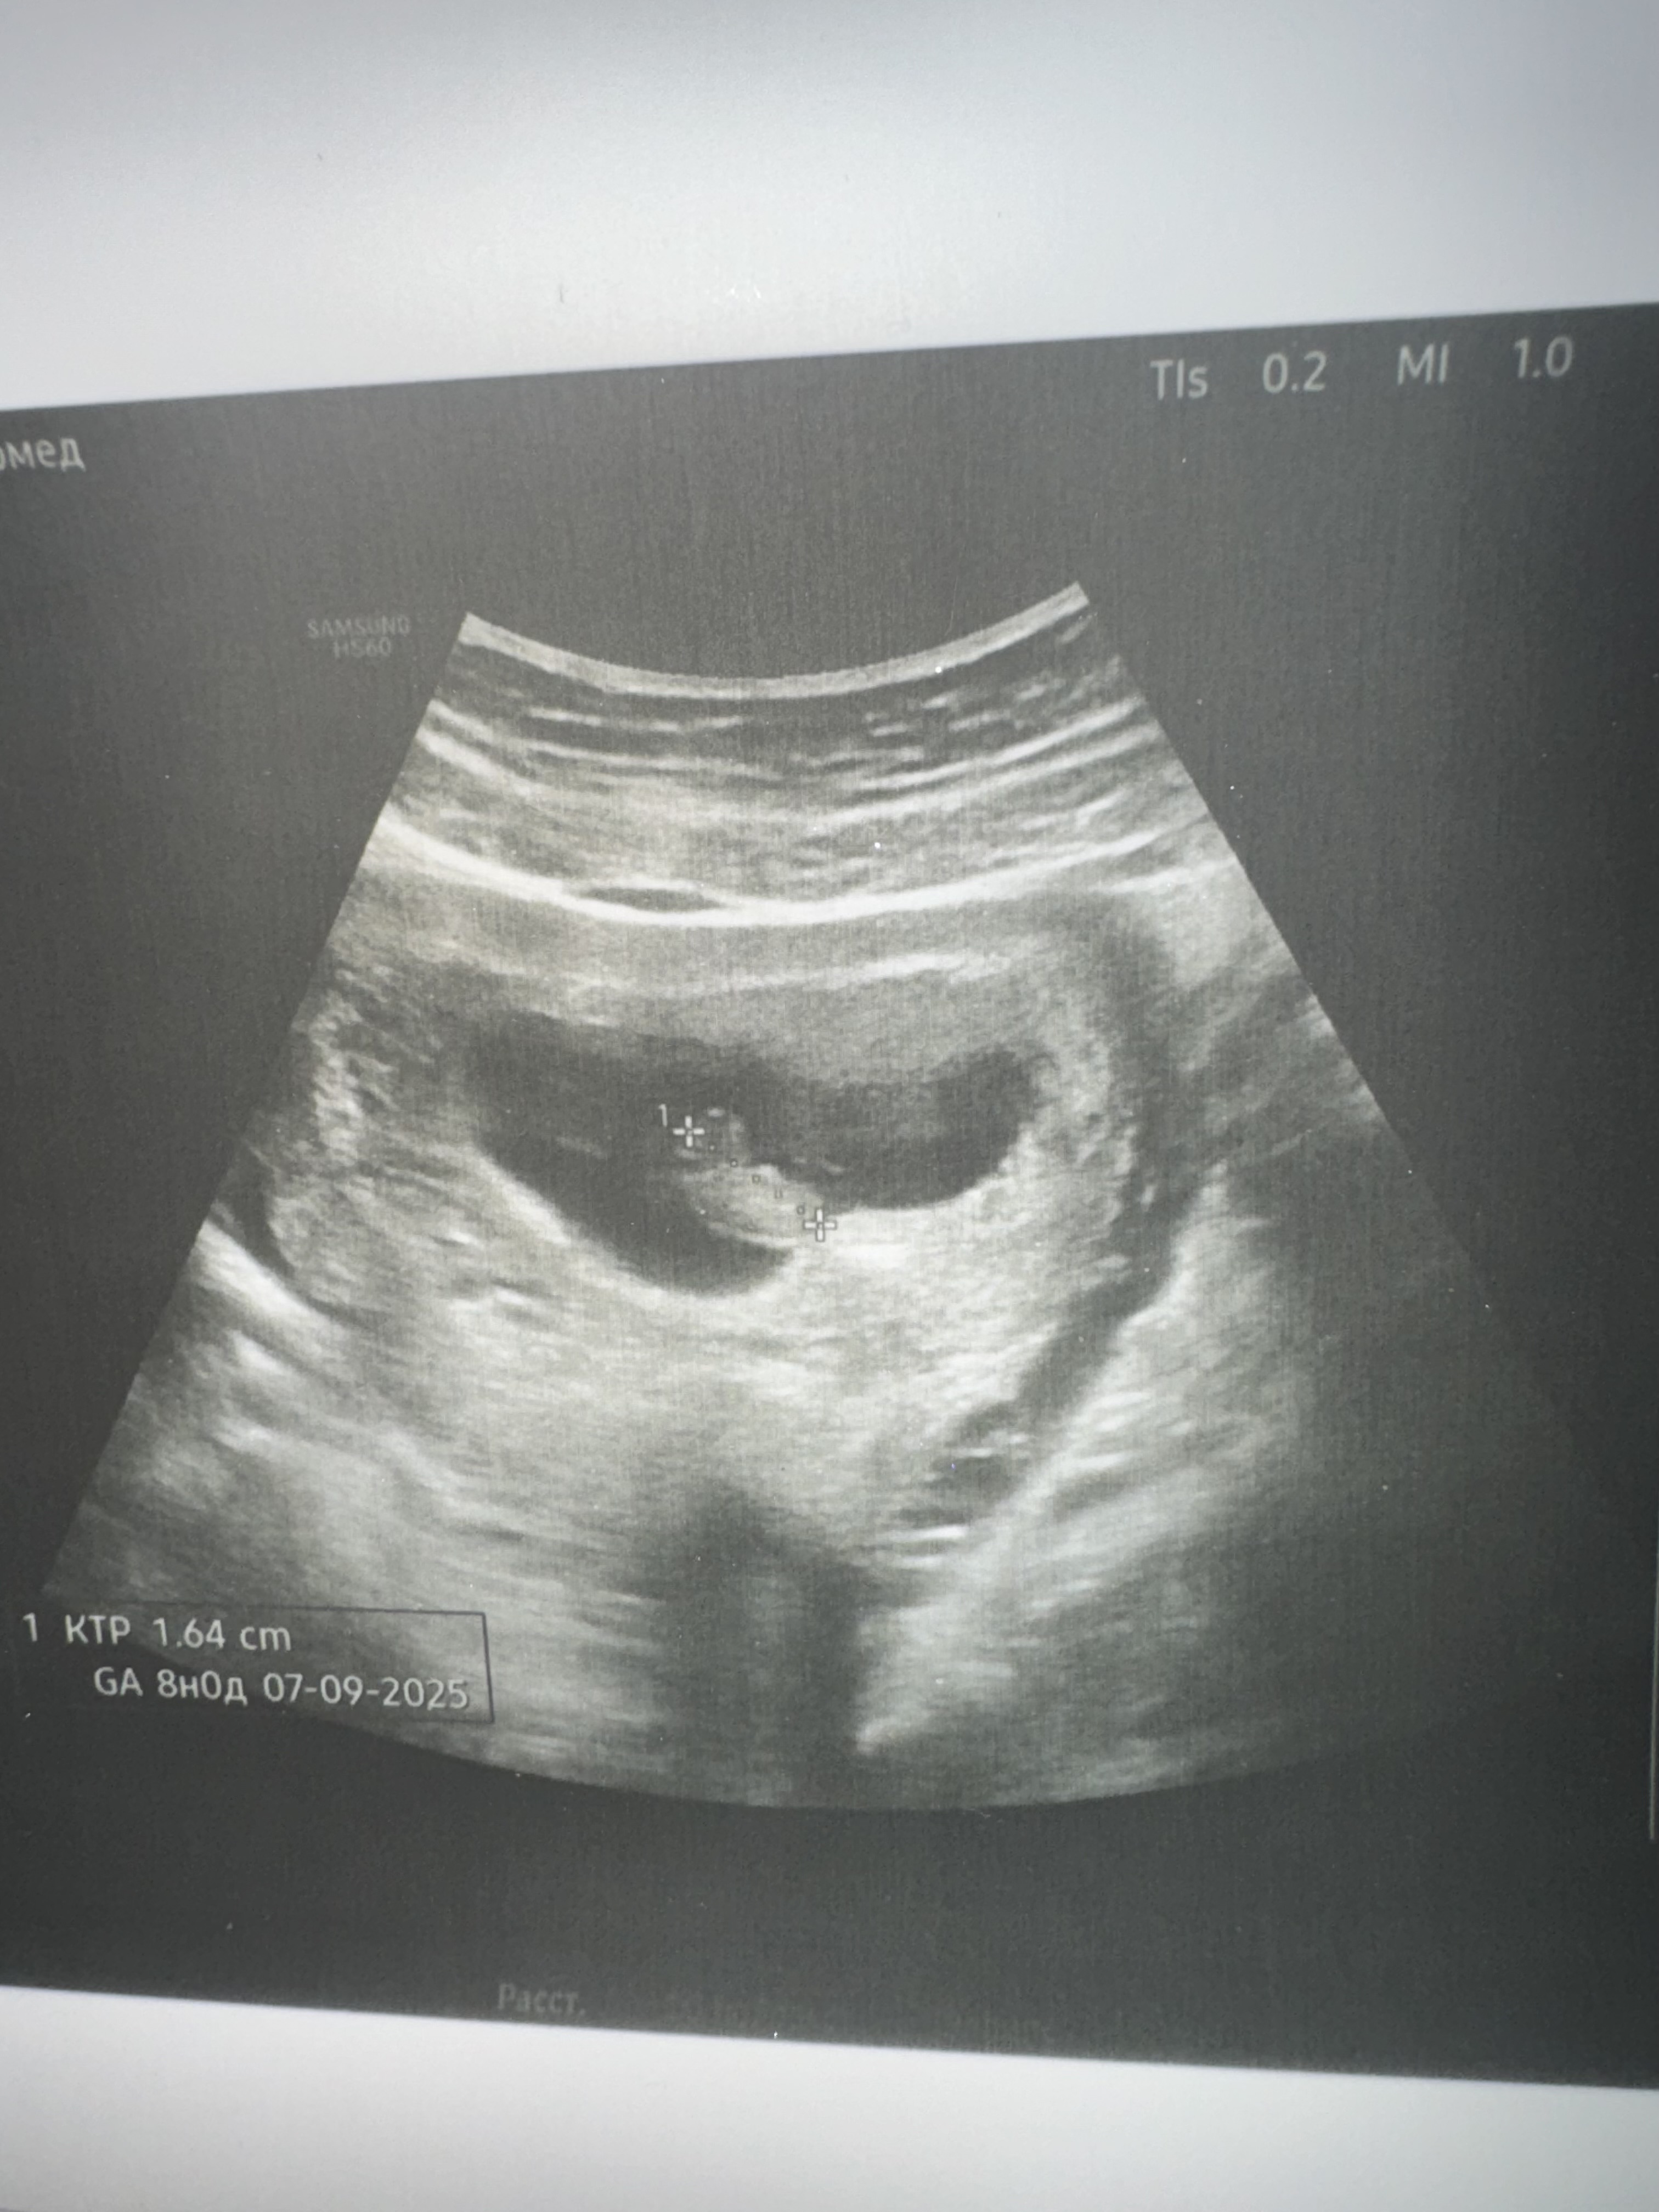

28 дпп. Узи. Двойня Нет сердцебиения